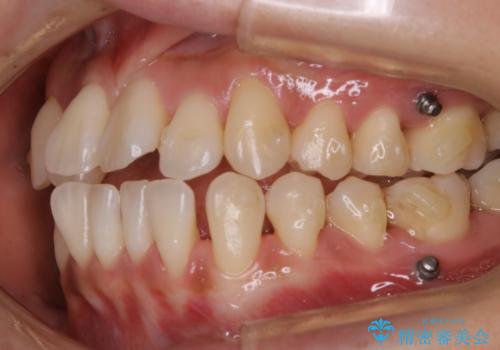

診査の結果、骨の厚みに余裕がなく幅の拡大とIPR(歯と歯の間を削り隙間を作る作業)のみでは歯周病に対する不安が残ることが懸念されたため、マイクロインプラントを用いて奥歯から順にすべての歯を後方移動させる方法によってスペースを作ることとなりました。

歯の遠心移動

歯を奥に移動させてスペースを作る方法を用いる場合、マウスピースの装着時間ならびに装着時の適合度がそれぞれ良い状態で保たれているかどうかが大きく関わってきます。

コンプライアンスが遵守されず、使用方法にバラつきがあるとマウスピースを作り直さなければいけなくなる可能性が上がってしまう傾向にあります。